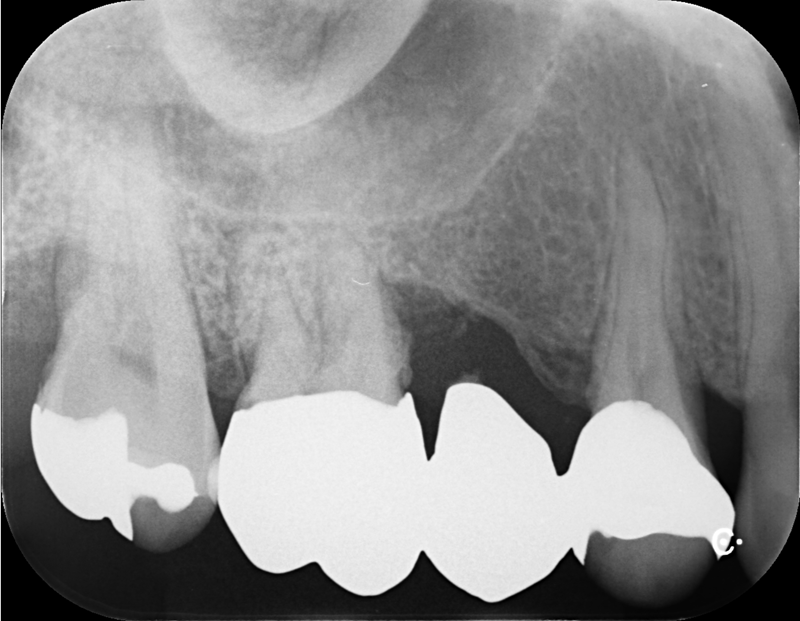

Case2

術前

術中

術後

| 治療名 | 再生療法 |

|---|---|

| 治療説明 | 右下6に重度の歯周病があり、通常の歯周治療でも改善しませんでした。歯周組織再生療法を行い、吸収してしまった骨を再生し、今後の歯周病の進行リスクを減らす事ができました。歯肉退縮もあったため同時に結合組織を移植し、骨と歯肉の再生を同時に行っています。 |

| 治療回数・期間 | 6ヶ月 |

| 副作用とリスク | 手術後に出血、腫脹、疼痛が生じることがあります。手術後は術部の創傷安定のためにブラッシング制限、食事制限があります。手術が複数回となることがあります。 |

| 料金(税込) | 再生療法:165,000円 結合組織移植:55,000円 総額:220,000円 |